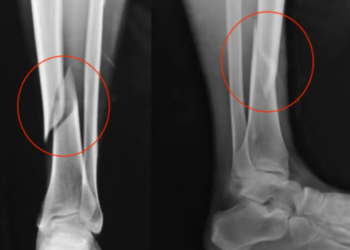

MANAUS - Uma vítima com fratura exposta ficou na chuva na noite deste sábado (18), esperando pelo Samu, depois de ...